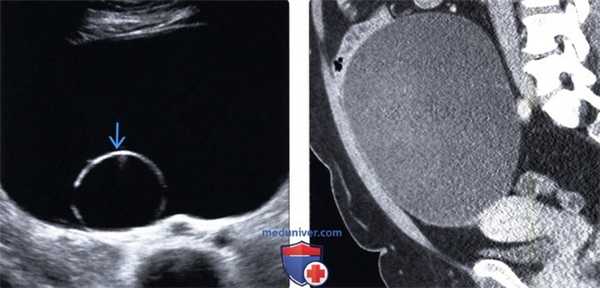

(Слева) В данном кистозном образовании яичника определяется одиночная тонкостенная камера. На трансвагинальной ультрасонографии определяется относительно небольшое количество внутренних эхосигналов в каждом отделе.

(Справа) КТ с контрастированием: определяется полное прорастание образования яичника, которое распространяется за пределы таза в средний отдел живота. Крупное образование яичника у женщины в пери- или постменопаузальном периоде является типичным проявлением муцинозной цистаденомы.

(Слева) При КТ с контрастным усилением в аксиальной плоскости у пациентки 53 лет, обратившейся по поводу пальпируемого объемного образования придатков, в правом яичнике выявляется киста, в стенке которой имеются мелкие очаги обызвествления.

(Справа) При КТ с контрастным усилением в корональной плоскости у той же пациентки в правом яичнике видна многокамерная киста с мелкими очагами обызвествления в перегородках. Обызвествление стенки овариальной кисты является признаком муцинозной опухоли и для серозных опухолей не характерно. (Слева) При МРТ на Т2-ВИ в аксиальной плоскости у пациентки 38 лет, которая обратилась по поводу пальпируемого объемного образования в малом тазу, визуализируется многокамерная киста с перегородками и без нодулярных утолщений стенки.

о Многокамерное кистозное образование с тонкой стенкой и тонкими перегородками

о Кисты содержат жидкость различной рентгеновской плотности